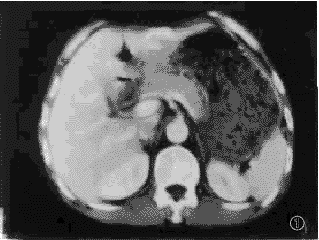

2.2.1 肝多发性血管瘤多期连续扫描表现:增强扫描中,血管瘤病灶共66个,其中21/66为小血管瘤,直径1.5~3.0cm,在增强扫描注射造影剂30秒、60秒时,15/21表现为均匀强化;有6/21表现为边缘不均匀强化,其中心可见低密度区。延迟至2分钟、5分钟扫描,病灶均表现为高密度或等密度灶。10~15分钟13/21表现为等密度,8/21表现为均匀低密度。44/66大血管瘤病灶,直径3.1~8.5cm,在30秒、60秒增强扫描,病灶边缘呈结节性强化,后期强化向中心扩展。37/44病灶在5~15分钟渐表现为等密度或稍低密度灶,8/44病灶延迟15分钟,中心仍见不规则低密度区。1/16例大血管瘤,直径4.2cm,在注射造影后,30秒、60秒表现为低密度,5~15分钟表现为边缘轻度强化(见图1~4)。

, 百拇医药

图1 多发性血管瘤.左外叶血管瘤病,30秒可见周边强化;

图2 左外叶血管瘤灶,60秒扫描病灶呈均匀高密度;

图3 右前叶血管瘤病灶,30秒可见病灶周边强化;

图4 60秒后病灶呈均匀高密度;